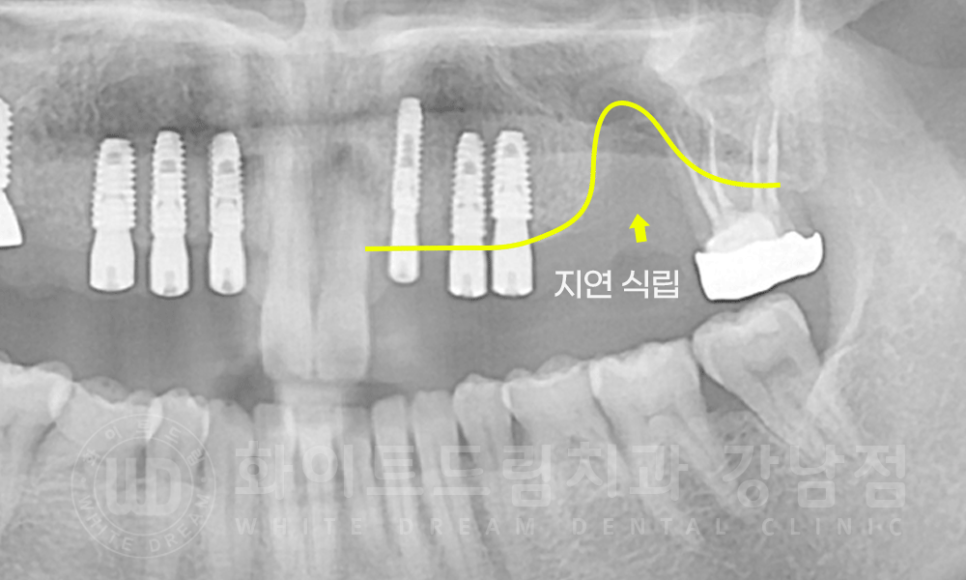

환자분의 x-ray 사진을 확인해 보겠습니다.

12 x 16번, 22 x 26번 치아가 각각 5unit 브릿지로 연결이 되어있습니다.

강남역 치과브릿지 / 치료 전 X-RAY

다만, 26번 치아 자리는 염증이 심해 골 소실도 심한 상태였습니다.

발치 후 해당 공간의 뼈가 차오르기를 3개월가량 기다린 후 수술을 진행하기로 했습니다.

3개월 뒤 26번 치아 잇몸뼈가 차오른 것을 확인한 후 수술에 들어갔습니다.

20.09.08 27번 식립